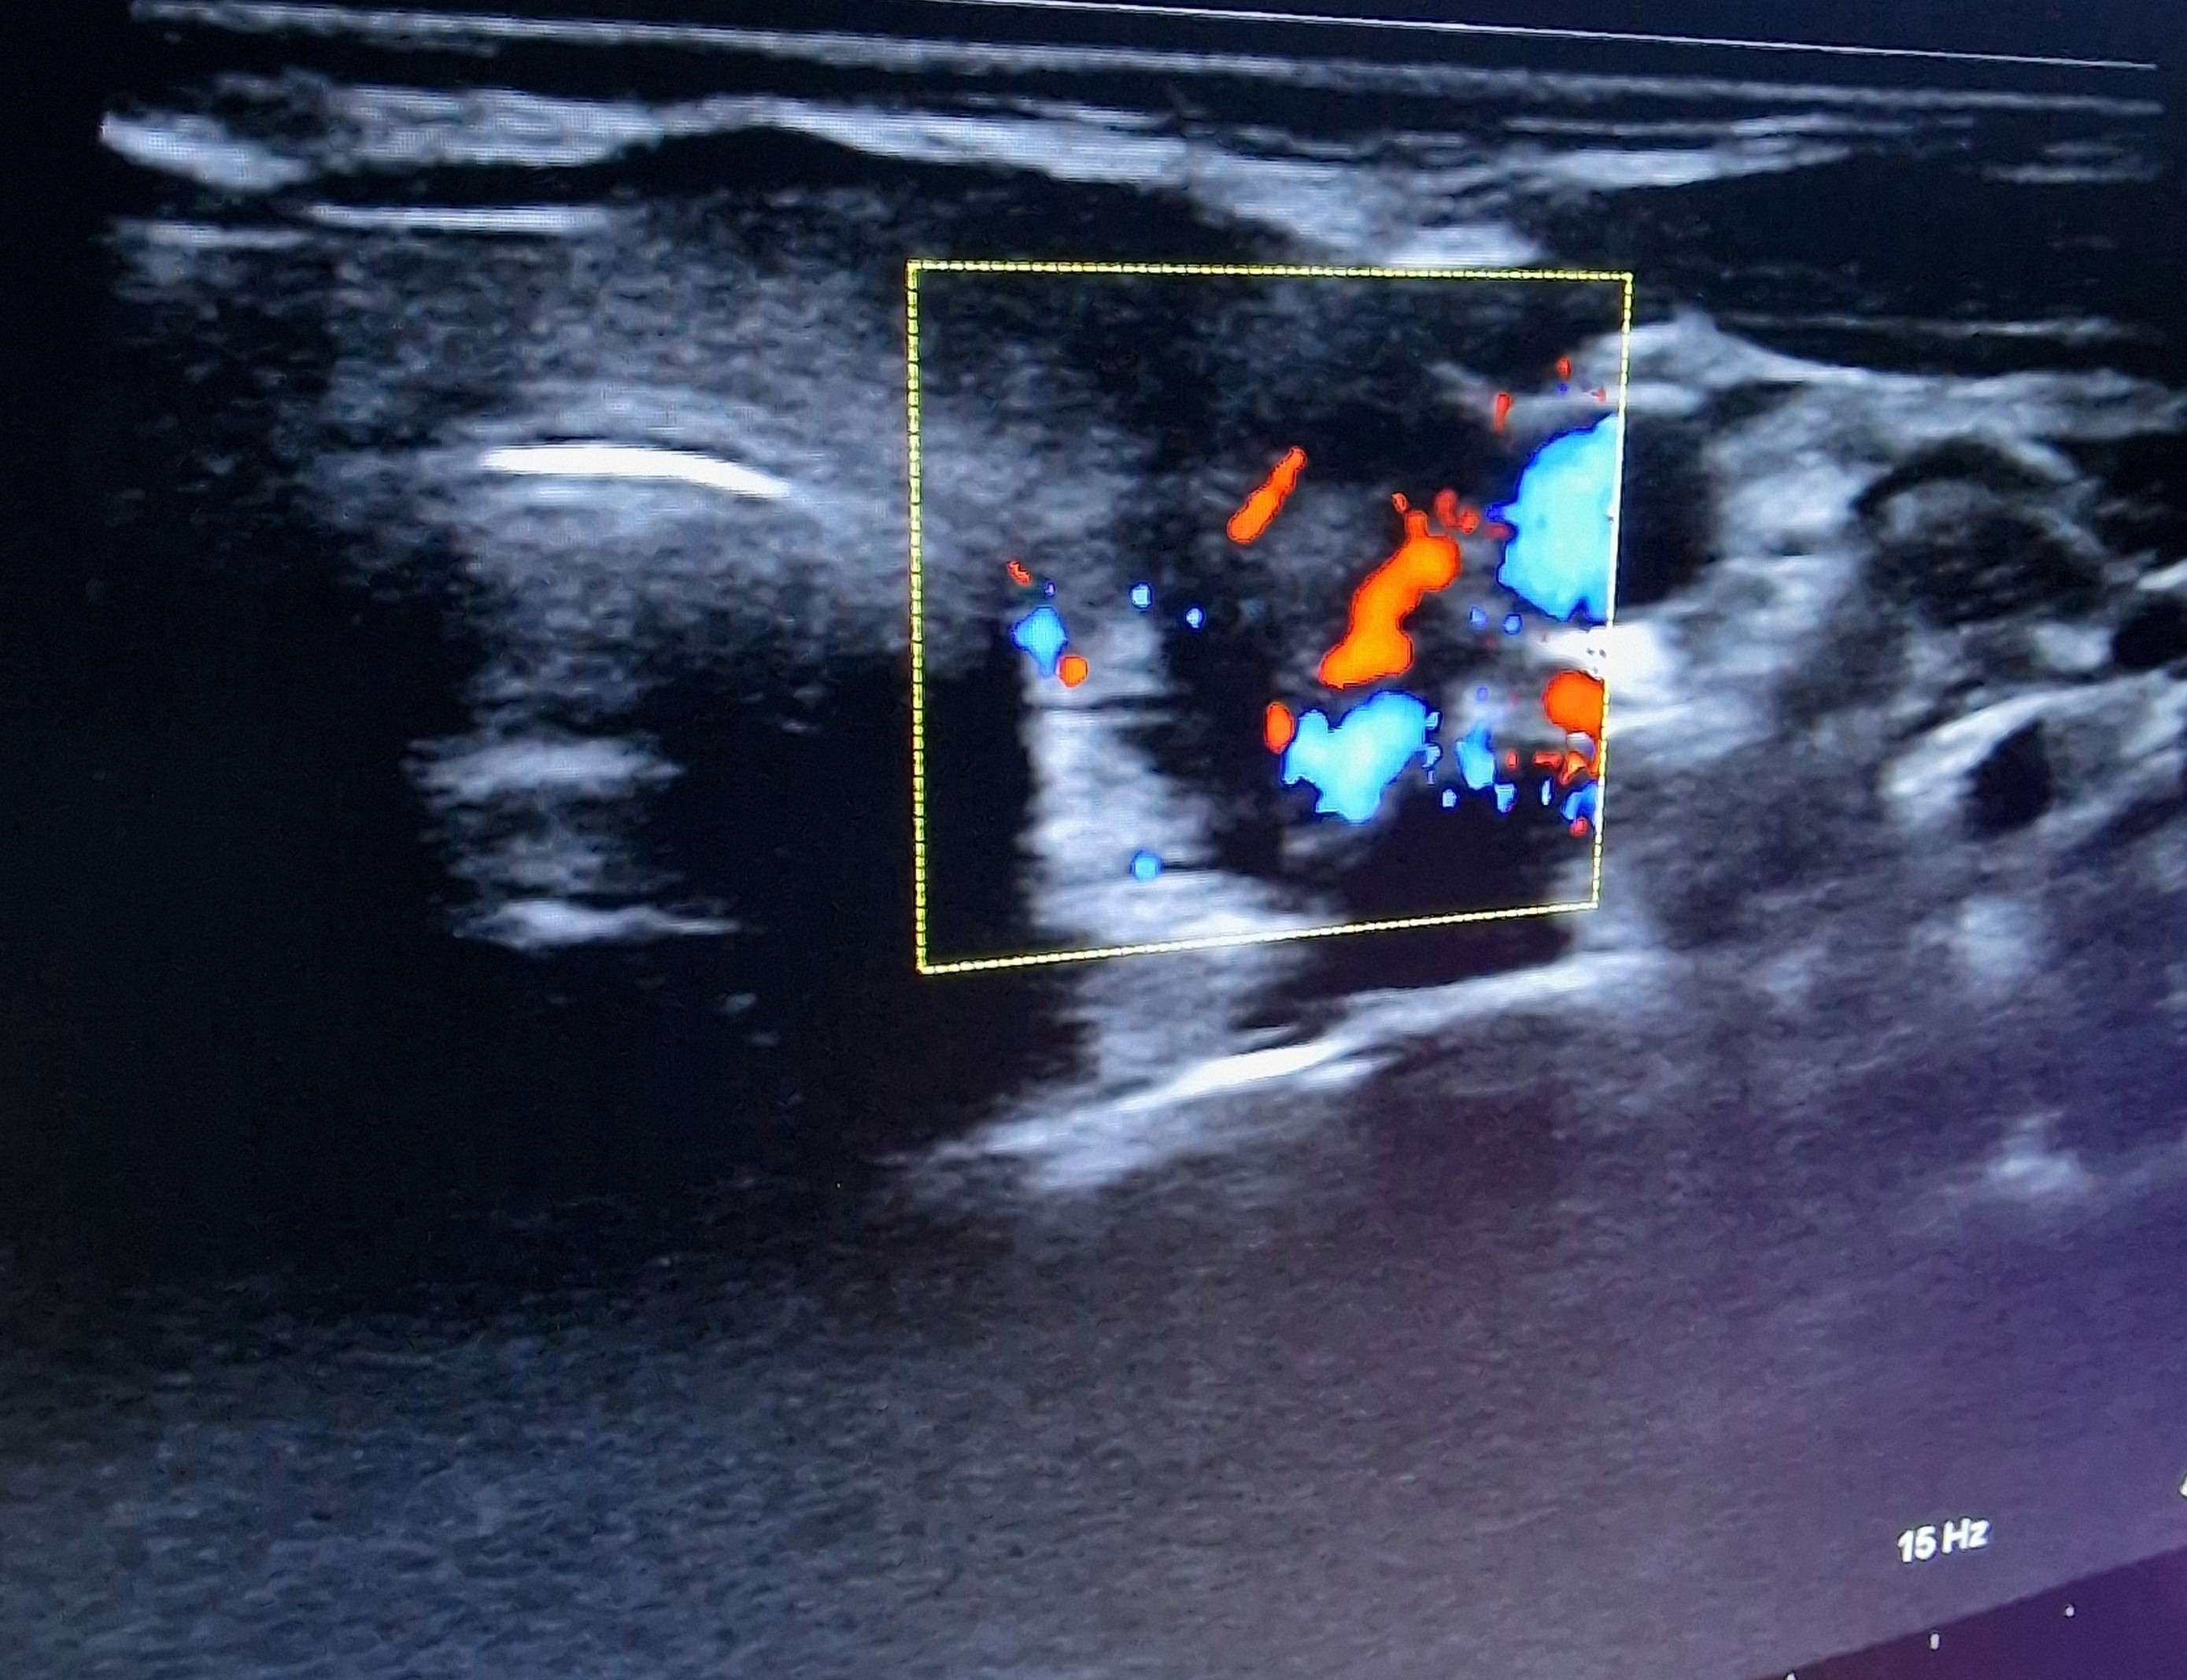

Ecografía cervical: tiroides de ecogenicidad heterogénea con áreas hipoecogénicas y ausencia de vascularización de éstas, Lóbulo Tiroideo Derecho 20 x 14 mm con nódulo < 10 mm no maligno e izquierdo 16 x 12 mm.

El diagnóstico diferencial se realizará con procesos infecciosos de vías respiratorias altas, con tiroidopatías con hipertiroidismo y ecogenicidad disminuida (enfermedad de Graves, patrón hipervascular; tiroiditis supurativa aguda), carcinoma tiroideo, hemorragia de nódulo tiroideo.

Ante cuadro de fiebre sin foco es importante un adecuado diagnóstico diferencial e historia clínica. Este tipo de tiroiditis es la causa más frecuente de dolor tiroideo, más frecuente en mujeres; de etiología desconocida, aunque frecuentemente aparece tras infección vírica de vías respiratorias altas. La ecografía es la prueba de imagen de elección para diagnosticarla, remarcando por tanto la utilidad de ella para el diagnóstico de patología sin sintomatología florida.